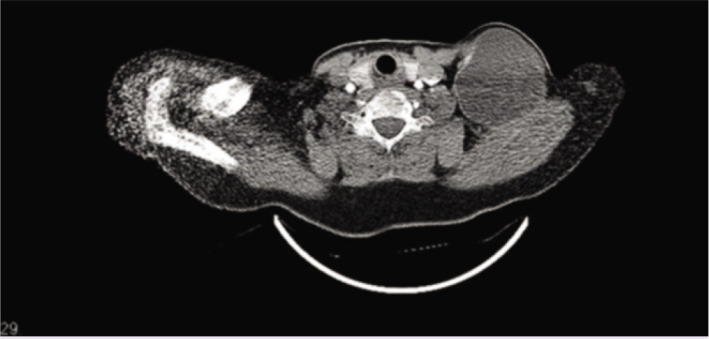

Neck cysts can be classified as congenital, infectious-inflammatory, and neoplastic. Hydatid disease is a parasitic infection caused by Echinococcus, is usually seen in the liver and lung and, is rare in the head and neck region even in endemic areas. If not treated, a life-threatening condition may be encountered. In this study, a case of hydatid cyst operated due to a cystic lesion with a diameter of approximately 8 cm in the neck was presented by reviewing the literature.